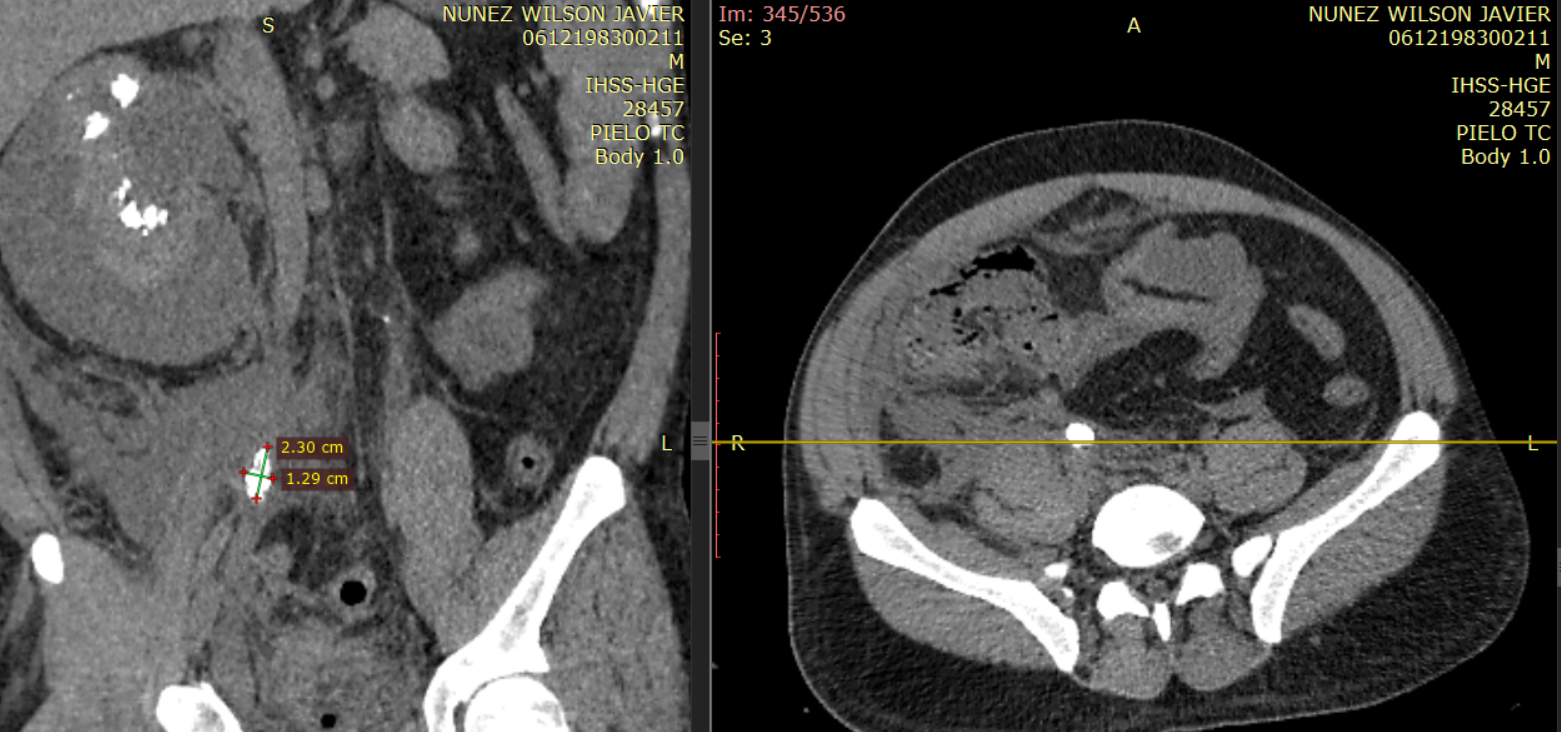

24 horas posterior a ingreso se ordena pielotomografía (no se realiza urotomografía por creatinina de 10mg/dl).

Imagen 6. Imagen de reconstrucción coronal de tomografía abdominal sin contraste (pielotomografia) donde se identifican imágenes hiperdensas en ambos riñones a nivel de pirámides renales, así mismo se observa la presencia de colección perirrenal derecha.

Ambos riñones se observan con presencia de imágenes hiperdensas en sitio anatómico de pirámides renales (valores de atenuación de hasta 1082UH) con presencia de colección perirrenal con densidad liquido (12UH) rodeando riñón derecho. Se observa estriación de la grasa en plano retroperitoneal derecho, extendiéndose hasta fosa iliaca derecha.

Presencia de Lito de grandes dimensiones en tercio medio de uréter derecho, con hidronefrosis secundaria. Atenuación (1500UH).

Imagen 8. Presencia de lito en tercio medio de uréter derecho, con dilatación retrograda del sistema colector.

Imagen 9. Presencia de lito en tercio medio de riñón izquierdo (contralateral) con dilatación retrograda del sistema colector ipsilateral.

Hallazgo que se encuentra del lado contralateral. Asociado a dilatación del sistema colector de forma bilateral.

Imagen 10 y 11. Muestran cortes axiales a diferentes niveles demostrando la presencia de litos en tercio medio de ambos urteres.